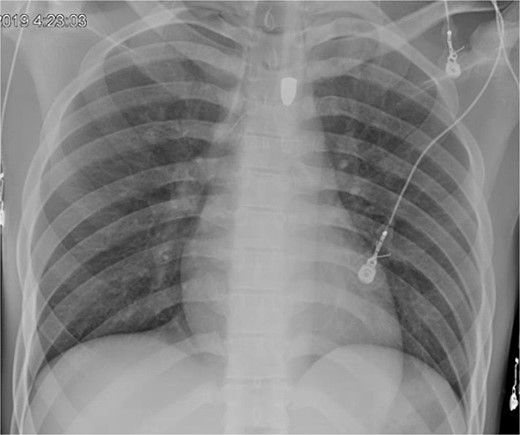

On hospital day (HD) 1, he developed ARDS and required intubation. He became hypotensive, raising concern for mediastinitis, but repeat imaging showed no new findings except that the bullet had migrated below the diaphragm (Fig. 3). Despite his septic appearance, his condition didn’t improve. He was diagnosed with severe AIDS (CD-4 count <100 cells/mm3) and multiple infections (hepatitis A, C, cytomegalovirus, toxoplasmosis, and multi-drug-resistant Pseudomonas pneumonia).